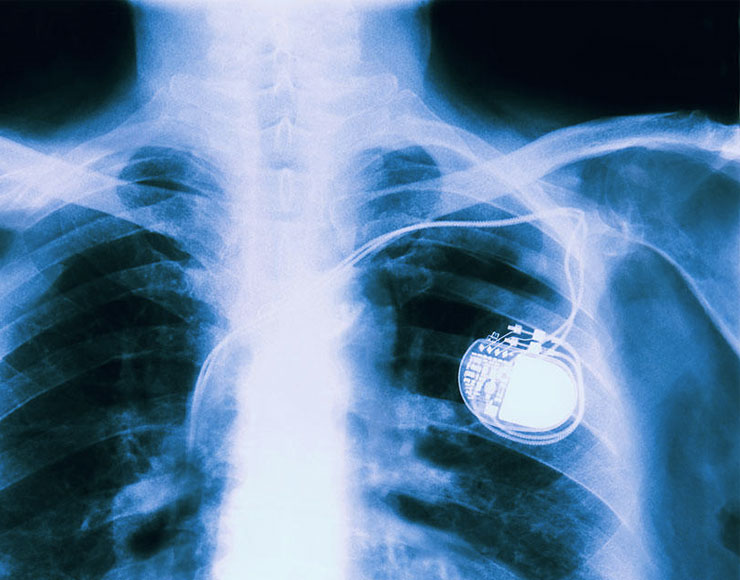

Pacemaker, pompe di insulina e altre apparecchiature impiantate, presentano problemi che rendono questi dispositivi vulnerabili ad attacchi informatici. Lo rivelano due diversi studi dei quali parla BBC News.

Il rapporto sui pacemaker ha analizzato dispositivi impiantabili di quattro produttori, così come l’ecosistema di attrezzatture che consentono di monitorarli e gestirli. Billy Rios e il Dr Jonathan Butts, della società di sicurezza Whitescope evidenziano “l’enorme sfida” per i produttori di pacemaker che dovranno integrare patch e risolvere bug potenzialmente utilizzabili da cybercriminali.

Solo pochi produttori hanno integrato funzionalità di cifratura o altri meccanismi che consentono di proteggere i dispositivi nella fase di monitoraggio e trasferimento dei dati. Nessun produttore dei dispositivi esaminati protegge i propri prodotti con login e password o esegue verifiche al fine di stabilire se il dispositivo al quale sono connessi è affidabile.

Spesso, spiega Rios, la minuscola dimensione e la bassa capacità di elaborazione di questi dispositivi rende difficile applicare standard che consentono di tenerli al sicuro. Si evidenzia ad ogni modo la necessità di integrare protezioni contro potenziali compromissioni dei sistemi, problematiche che potrebbero avere implicazioni nella cura del paziente.